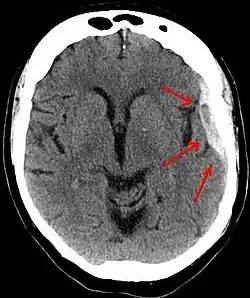

A subdural hematoma demonstrated by CT

Subdural hematomas occur most often around the tops and sides of the frontal and parietal lobes.[3][2] They also occur in the posterior cranial fossa, and near the falx cerebri and tentorium cerebelli.[3] Unlike epidural hematomas, which cannot expand past the sutures of the skull, subdural hematomas can expand along the inside of the skull, creating a concave shape that follows the curve of the brain, stopping only at dural reflections like the tentorium cerebelli and falx cerebri.

On a CT scan, subdural hematomas are classically crescent-shaped, with a concave surface away from the skull. However, they can have a convex appearance, especially in the early stages of bleeding. This may cause difficulty in distinguishing between subdural and epidural hemorrhages. A more reliable indicator of subdural hemorrhage is its involvement of a larger portion of the cerebral hemisphere. Subdural blood can also be seen as a layering density along the tentorium cerebelli. This can be a chronic, stable process, since the feeding system is low-pressure. In such cases, subtle signs of bleeding—such as effacement of sulci or medial displacement of the junction between gray matter and white matter—may be apparent.

Fresh subdural bleeding is hyperdense, but becomes more hypodense over time due to dissolution of cellular elements. After 3–14 days, the bleeding becomes isodense with brain tissue and may therefore be missed.[20] Subsequently, it will become more hypodense than brain tissue.[21]